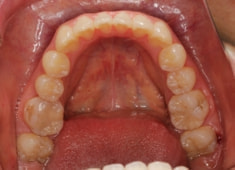

治療後(2年後)